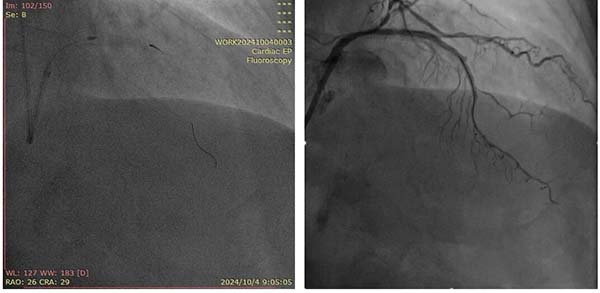

微导管头端断裂(左)冠脉血运重建(右)